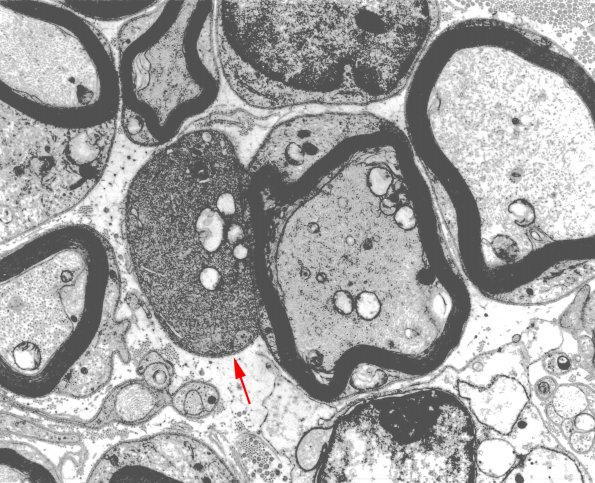

Washington University Experience | PERIPHERAL NEUROPATHY | 5 AXONAL REGENERATION | 12A2 EM 40 brighter copy - Copy

Higher magnification of image #12A1. (electron micrograph)